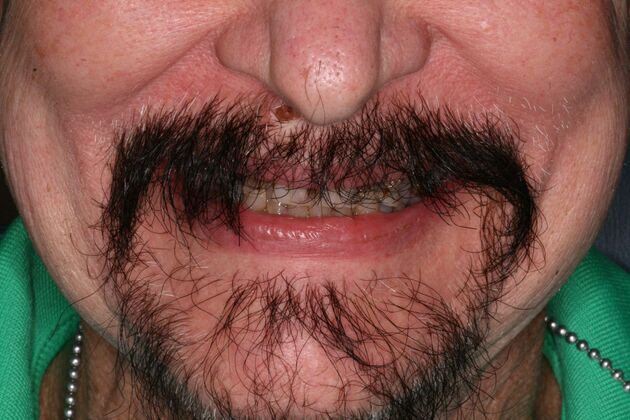

Patient had severe cavities throughout the mouth due to extreme dry mouth and history of use of tobacco. Patient was very discouraged as he had hated the idea of wearing dentures. Patient found Dr Bidra online and sought treatment and had all his teeth extracted and implants placed and new teeth installed all in 1 day! Patient was extremely satisfied with his transformation and eradication of all disease and bacterial infections.

Procedures : extractions, implants, All on 4 , Teeth in a day, no bone grafting and full mouth reconstruction with monolithic zirconia bridges.